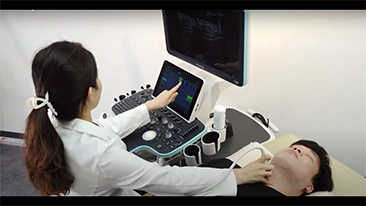

Desde que se fund├│ la compa?├Ła, Mindray ha explorado incansablemente nuevas formas de mejorar la confiabilidad del diagn├│stico. Con la revolucionaria tecnolog├Ła de ZONE Sonography?, la nueva plataforma ZST+ de Resona?7 lleva la calidad de la imagen por ecograf├Ła a un nivel superior mediante el procesamiento de datos de canal y la adquisici├│n de zona.

Adem├Īs de la calidad de imagen de primer nivel, Resona?7 tambi├®n mejora las capacidades de investigaci├│n cl├Łnica con el revolucionario V?Flow para la evaluaci├│n hemodin├Īmica vascular y con la adquisici├│n de planos m├Īs inteligente a partir de conjuntos de datos 3D para el diagn├│stico del SNC fetal. Al combinar el funcionamiento multit├Īctil basado en gestos m├Īs intuitivo y todas las caracter├Łsticas cl├Łnicas esenciales, Resona?7 realmente lidera las novedades en innovaci├│n de ecograf├Łas.